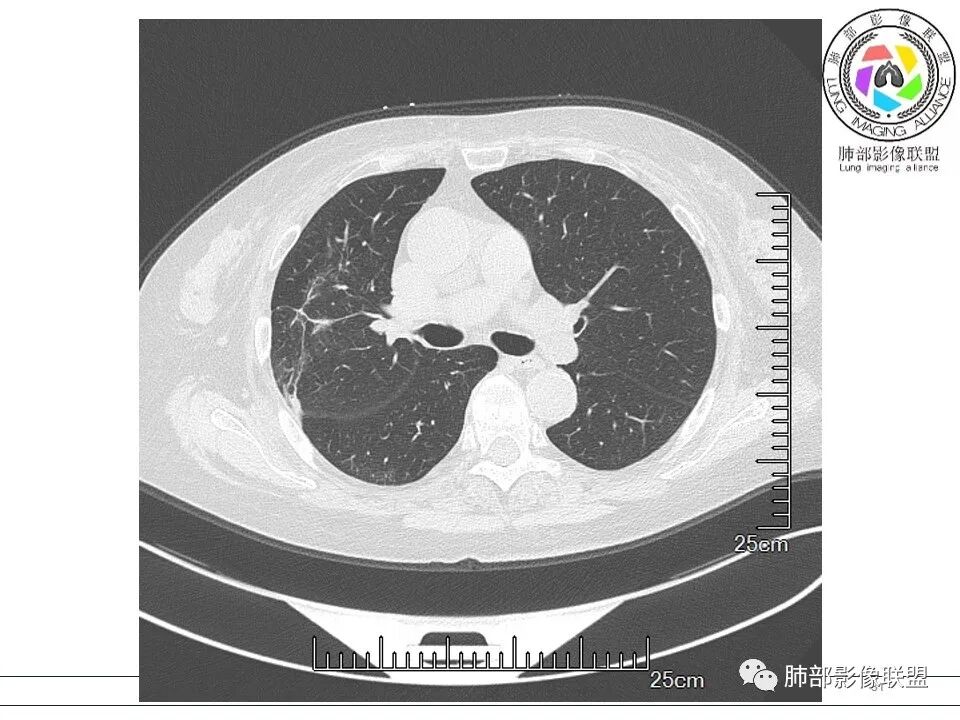

南边: 这个病例大方向没问题,炎性。目前大家都是考虑:隐球菌病、OP,其实这两个结论有重叠,而且这个病例很值得讨论,可惜,估计没有证实。影像特点:病灶长轴与胸膜平行,侧向融合特点明显,符合隐球菌病,问题是目前的状态,边缘收缩明显

内部支气管扩张,周围少量GGO,而且病灶离开了胸膜,附近长索条影,支持机化的改变

问题是:需要抗真菌?还是按OP治疗?我个人认为这阶段的改变目前不是病原菌引起的,而是炎性反应后期修复的改变,应该抗OP为主

5、分布:隐球菌肺炎是肺泡性炎症,病灶分布多位于胸膜下,可紧贴胸膜,也可与胸膜邻近,病灶长轴与胸膜平行。(划重点,分布特点非常重要,因为隐球菌如果没有荚膜,会被巨噬细胞吞噬,在人体内是无法生存。隐球菌孢子吸入后,要有高浓度的CO2的条件下,才能形成荚膜,所以肺泡内、胸膜下多见)

6、支气管和血管:支气管通畅或进入后堵塞,增强可见血管造影征或血管影消失。